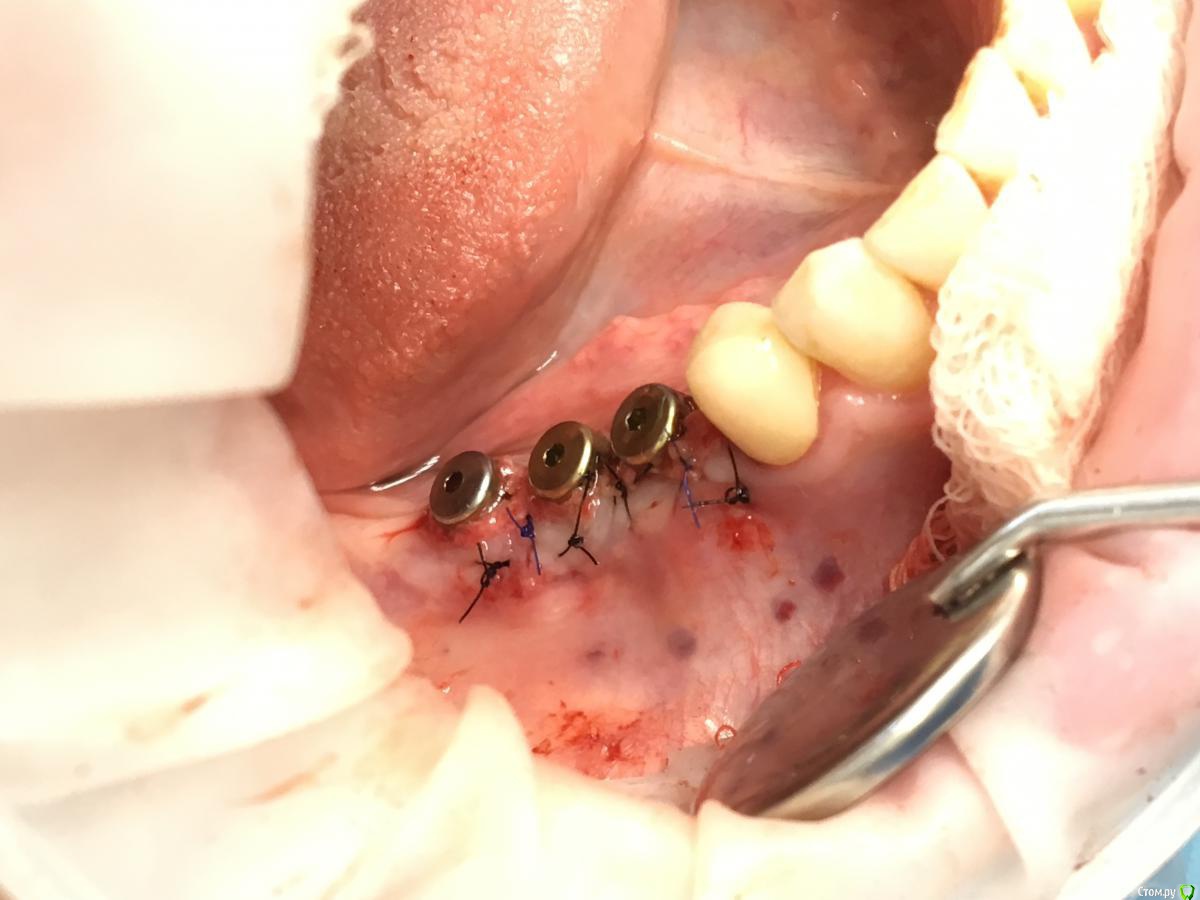

Shakirbura Опубликовано 4 мая, 2018 Автор Поделиться Опубликовано 4 мая, 2018 Закончу кейс, раз уж начал...Оставил импланты на 4 месяца.Провел смещение лоскута, а через месяц раскрыл с ФДМ и ССТ.Вот что получилось. Всем спасибо. 7 Ссылка на комментарий

Bier Опубликовано 4 мая, 2018 Поделиться Опубликовано 4 мая, 2018 ну ничего так косточка то наросла )) Ссылка на комментарий

Shakirbura Опубликовано 4 мая, 2018 Автор Поделиться Опубликовано 4 мая, 2018 ну ничего так косточка то наросла ))Да, душевная) Только целый год на это дело потратили..... Ссылка на комментарий